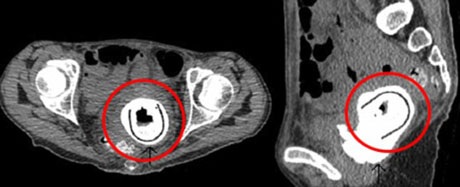

Hình ảnh chụp X-quang cho thấy vật thể lạ trong người một bệnh nhân.

Các bác sĩ đã yêu cầu cô chụp X-quang và họ phát hiện ra một vật thể hình ô van dài 12,7 cm trong cơ thể người phụ nữ. Đây là loại đồ chơi tình dục mà nữ bệnh nhân khẳng định đã ngừng sử dụng suốt 10 năm qua.

Vật thể lạ, nhô ra từ âm đạo vào bàng quang của bệnh nhân, khiến cô phải chịu đựng nhiều triệu chứng hiếm gặp có tên là “rò bàng quang âm đạo”, đồng nghĩa rằng nước tiểu có thể chảy vào âm đạo.